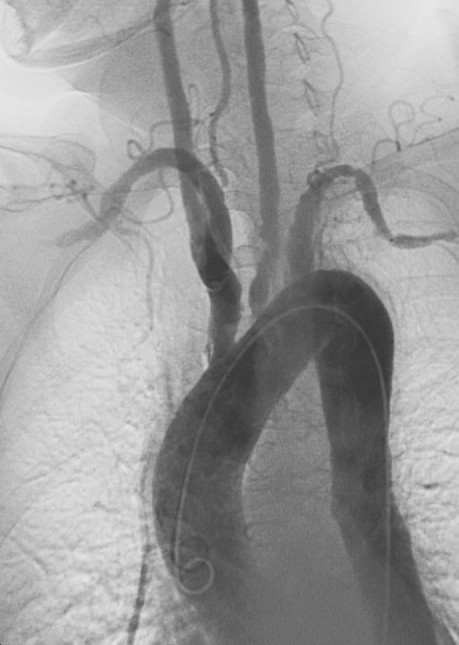

De diagnose wordt gesteld op het arteriogram waarbij focale

of segmentale vernauwingen of occlusie zichtbaar zijn in de aorta of directe

aftakkingen of de grote arteriën van de extremiteiten, niet verklaard door andere

oorzaken zoals atherosclerose. In Japanse definities wordt het criterium jonger

![Takayasu arteritis (click on photo to enlarge) [source: Weiss PF, Corao DA, Pollock AN, Finkel TH, Smith SE - Wikimedia - Creative Commons License 2.0] Takayasu arteritis](../../../images/Takayasu-arteritis-3z.jpg) |

Takayasu

arteritis |

Röntgenfoto's: Justin Ly en Weiss PF. et al. - Wikimedia (Creative

Commons License

1.0

/

2.0).